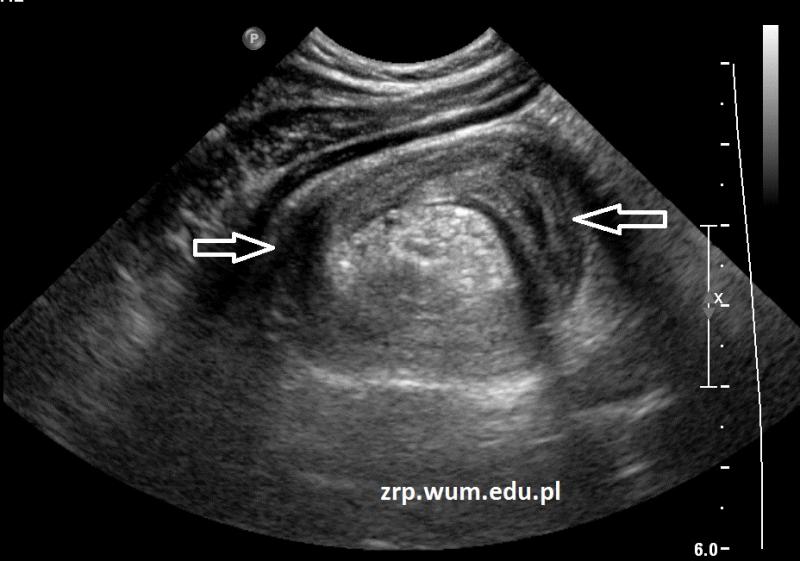

Rozpoznanie: W badaniu USG uwidoczniono wgłobienie krętniczo-kątnicze (białe strzałki).